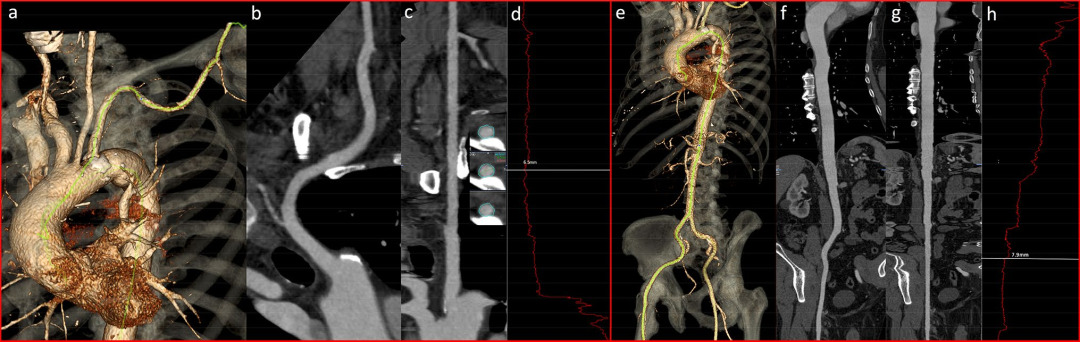

主动脉和外周血管通路

在术前 TAVI 评估中,非侵入性影像学检查在准确评估血管通路方面起着重要作用。为了最大限度地降低围术期和术后并发症的风险,准确的入路选择是手术能否进行和成功的最重要组分之一。CT比传统的单平面血管造影更准确,其能允许2D和3D重建,以最佳评估血管最小内径,血管曲折度,严重程度,动脉粥样硬化的延伸程度和形式,并识别高风险特征,包括夹层和复杂动脉粥样硬化斑块(图7)。此外,CT很容易排除先天性解剖变异(如,主动脉弓离断,牛型弓,双主动脉弓,主动脉缩窄,右或左锁骨下动脉畸变,镜像右弓)和其他主动脉异常(如动脉瘤,动脉粥样硬化/血栓形成),这可以确定最佳的血管通路。经股动脉入路仍然是所有器械的首选方法。经锁骨下动脉、颈总动脉和头臂干是TAVI的两种替代入路,而经左心室心尖入路仅适用于SAPIEN装置。经微型胸骨切开术的微创经主动脉通路是最近适用于两种装置的替代入路,其入口点在环平面上方约6厘米处。可用的设备输送系统有不同的套管尺寸,具体取决于制造商和设备的生产版本。理想情况下,原生血管的最小内径应大于所选输送套管的外径。环状的动脉粥样硬化壁钙化(或马蹄形样)、原生血管直径小和血管显著扭曲是手术并发症的危险因素,如果存在两种或两种以上特征,则必须考虑其他入路(即经心尖、经主动脉)。血管并发症是经股动脉TAVI最常见的并发症(包括瓣周反流和卒中)。外周通路的CT分析必须通过标准化方法进行,包括3D成像,曲线多平面重建和用于钙化的最大密度投影,所有测量均在血管的正交平面(横截面)中进行,以获得更准确的评估。CT对于确定假体瓣膜植入的最佳透视角度也很有价值,如图8所示。

图7:评估锁骨下动脉(a-d) 和股动脉(e-h) 通路。三维体积渲染 CT 图像 (a, e) 提供了对动脉树曲折度的直观视觉评估,能检测任何急转角。曲线多平面重建(CPR,b,f)和拉直的 CPR(c,g)能识别任何狭窄或动脉瘤扩张,并识别最小口径的血管束。一些应用程序在整个过程中(d,h)的每个点提供血管平均直径的自动外推,因此实施并加快了最小直径点的识别。